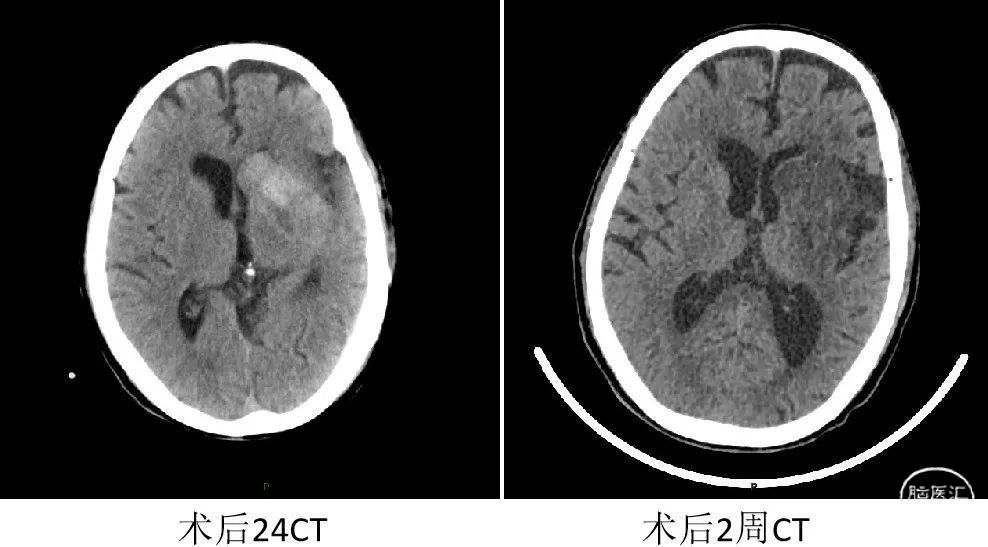

术后24小时复查CT提示未见出血,改为阿司匹林+波立维双重抗血小板聚集治疗。

出院时查体:BP134/74mmHg,HR86次/分,神志清醒,查体合作,应答切题,构音欠清。眼球活动正常,无凝视,无眼震,右侧鼻唇沟稍浅,口角向左歪斜,伸舌偏右。心脏各瓣膜听诊区未闻及病理性杂音。左侧肢体肌力5级,右侧肢体肌力3级,右肢肌张力稍弱。NIHSS评分5分。

出院60天随访:神志清楚,言语功能恢复,右侧肢体肌力4级。